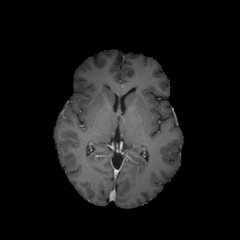

Objectives: This work aims to explore the impact of multicenter data heterogeneity on deep learning brain metastases (BM) autosegmentation performance, and assess the efficacy of an incremental transfer learning technique, namely learning without forgetting (LWF), to improve model generalizability without sharing raw data. Materials and methods: A total of six BM datasets from University Hospital Erlangen (UKER), University Hospital Zurich (USZ), Stanford, UCSF, NYU and BraTS Challenge 2023 on BM segmentation were used for this evaluation. First, the multicenter performance of a convolutional neural network (DeepMedic) for BM autosegmentation was established for exclusive single-center training and for training on pooled data, respectively. Subsequently bilateral collaboration was evaluated, where a UKER pretrained model is shared to another center for further training using transfer learning (TL) either with or without LWF. Results: For single-center training, average F1 scores of BM detection range from 0.625 (NYU) to 0.876 (UKER) on respective single-center test data. Mixed multicenter training notably improves F1 scores at Stanford and NYU, with negligible improvement at other centers. When the UKER pretrained model is applied to USZ, LWF achieves a higher average F1 score (0.839) than naive TL (0.570) and single-center training (0.688) on combined UKER and USZ test data. Naive TL improves sensitivity and contouring accuracy, but compromises precision. Conversely, LWF demonstrates commendable sensitivity, precision and contouring accuracy. When applied to Stanford, similar performance was observed. Conclusion: Data heterogeneity results in varying performance in BM autosegmentation, posing challenges to model generalizability. LWF is a promising approach to peer-to-peer privacy-preserving model training.